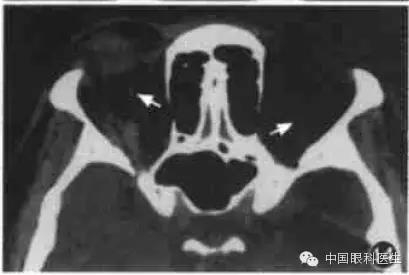

10.甲状腺相关眼病

甲状腺相关眼病也称Graves'病,这是最常见的单侧和双侧眼球突出原因。临床上有眼睑退缩、上睑迟落等一些典型体征。而CT在疾病的不同时期显示出不同的形态学的改变,主要CT征包括:眼球突出、眼外肌肥厚、脂肪垫扩大,其中以眼外肌肥厚最常见(图12)。其受累频率依次是下直肌、内直肌、上直肌和外直肌,晚期提上睑肌、上斜肌均肥厚。甲状腺相关眼病的眼外肌肥厚特征为以肌腹梭形肥厚为主,边界清楚。但当下直肌肥厚做水平CT扫描时,易误诊为眶内肿瘤,此时应做冠状CT鉴别。

图12甲状腺相关眼病CT显示双侧内外直肌肌腹和眶尖部增厚,视神经受压,筛骨纸板向内移位(箭头)